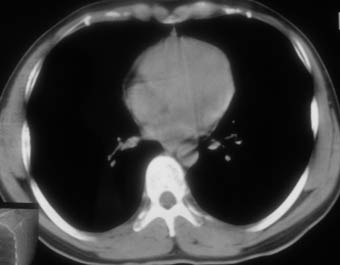

锁骨骨折复查,发现肺内高密度影,行ct检查。

男性,35岁,无任何感觉,无明显发热感冒病史。

纵隔窗!

右肺下叶背段斑片状阴影,边缘模糊,纵隔内未见肿大淋巴结,病人无发热及感冒史,要考虑浸润型肺结核,可结合ppd检查,或短期抗炎治疗复查。

右肺下叶背段长椭圆型病灶,边缘较规则,无明显分叶征、毛刺,远段未见阻塞征象,病灶较松散,纵隔窗明显小于肺窗,年龄35岁,支气管稍示变窄,纵隔内未见明显肿大淋巴结,这些都不支持肿瘤。病人无任何感觉,无明显发热感冒病史,首先考虑结核(也是结核好发部位),慢性炎症不能完全除外。